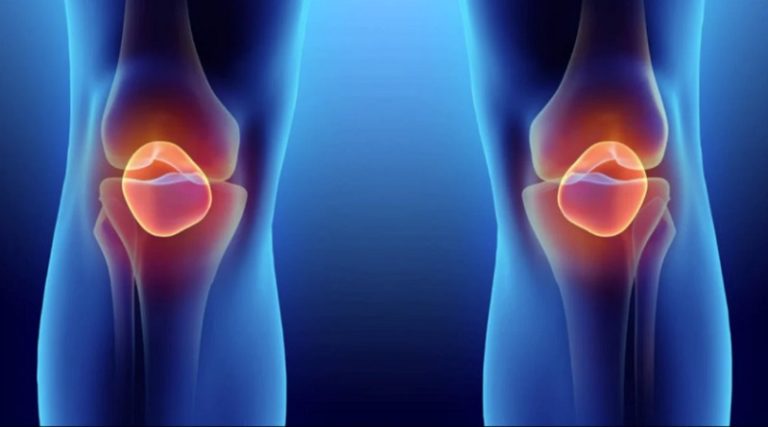

Uno de los problemas que afecta al ser humano a medida que envejece, son las articulaciones, y siempre está en la búsqueda de sustancias naturales, métodos de alimentación o ejercicios que ayuden a ralentizar el desgate del cuerpo y sus coyunturas.

Según un informe de la Medline Plus, una página de la Biblioteca Nacional de Medicina del Instituto Nacional de Salud (NIH, por sus siglas en inglés) del Gobierno de Estados Unidos, indicó que la glucosamina es una sustancia química que se encuentra en el cuerpo, la cual produce otras sustancias químicas que forman tendones, ligamentos, cartílagos y el líquido que rodea las articulaciones y ayudar a prevenir su degradación.

Las personas comúnmente usan sulfato de glucosamina y clorhidrato de glucosamina para la osteoartritis. También se usa para el dolor articular, la artritis reumatoide, la esclerosis múltiple y muchas otras condiciones, pero no existe una buena evidencia científica que respalde estos otros usos.